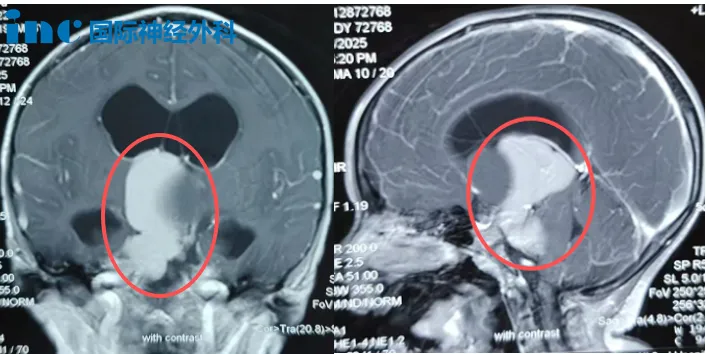

术前MRI检查显示,小安颅内存在大型占位病变。此刻,这位勇敢的孩子正以其顽强生命力,逐步走向康复。

这条"颅内虫子"引发持续头痛、呕吐症状,导致发育迟滞和四肢肌力减弱。影像学检查显示,肿瘤从鞍上区域延伸至第三脑室和桥小脑角区,并已引发脑积水。随着"虫子"向"生命禁区"脑干生长,小安症状日益加重:呕吐变得剧烈,头痛持续发作,右腿活动逐渐不灵,行走时常跌倒。家人精心呵护小安,但这条"虫"从未停止侵害。

"所幸患儿目前视力与视野均正常,这表明视神经未遭受实质性损伤,这是非常积极的指征。"但巴特朗菲教授郑重提醒,"从大量临床病例来看,如此程度的脑积水极易突发失代偿:可能今日情况尚可,明日急转直下。病情变化随时可能发生,因此手术需要尽快实施。"